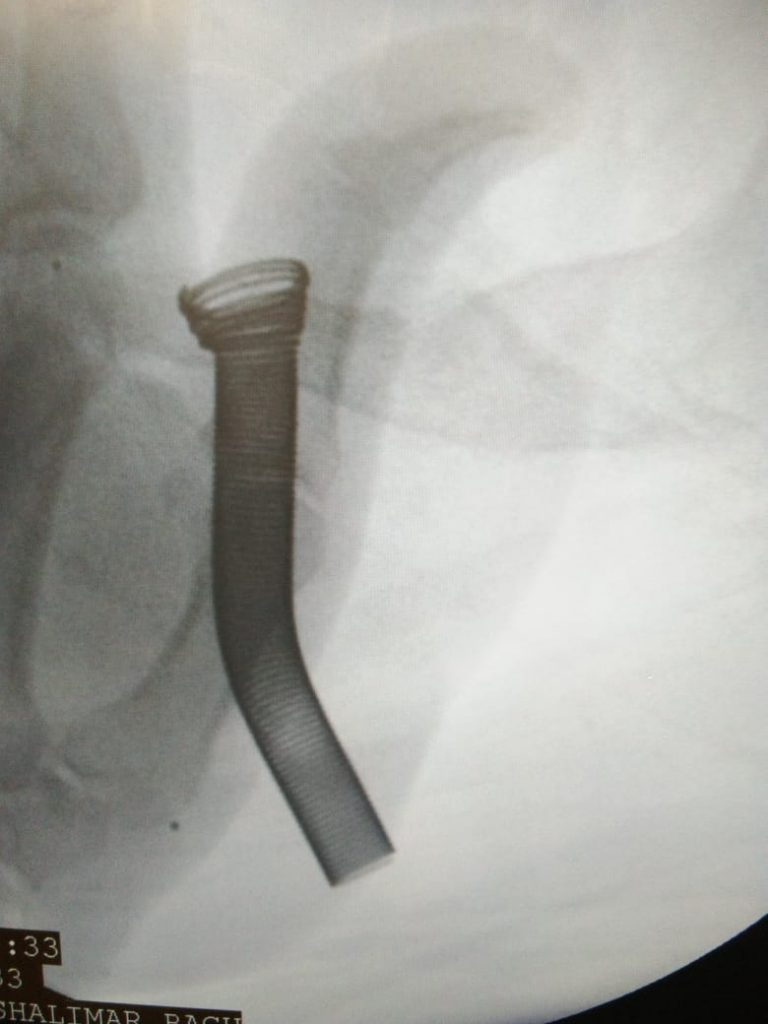

Memokath placement for complex urethral strictures and BPH patients(not fit for anaesthesia)